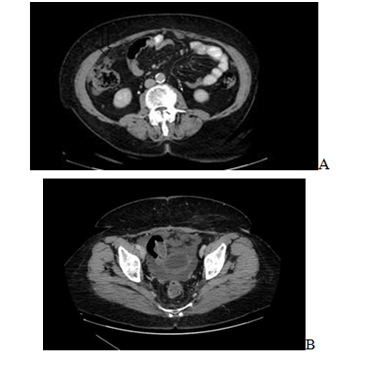

A 69years old woman is visited for diffuse abdominal pain, weight loss and anorexia associated with epigastralgia and difficult alvus. In remote anamnesis she has had a complete isteroannessiectomy for cancer 20years ago allow by CHT plus RT. She had only arterial hypertension and mild obesity as comorbidities. At objective exam her abdomen was normal with no mass in rectum at digital exploration. Gastroscopy and colonoscopy were negative and ematochimic exams were normal with tumoral markers as Ca 15.3 40ng/ml, Ca 19.9 108ng/ml, Ca 125 23ng/ml. She was submitted at CT SCAN which demonstrated mild ascites and some nodules in the Glissonian capsula in VI-VIIVIII segment, in right parieto-colic and pararectal region and in omentum (Figure 1). For this reason she was subjected to exploratory laparoscopy which demonstrated diffuse mucinous carcinosis in the same region as CT scan with implication of the appendix (Figure 2). Peritoneal biopsy and histological finding revealed diagnosis of Pseudomyxoma Peritonei. Then she was studied and prepared for laparotomy with pneumological and cardiologic visit plus echocardiography which revealed only arterial calcification and after a new toraco-abdominal CT scan for staging that demonstrated two specific pulmonary nodules in right superior lobe and left lateral lobe respectively 6mm and 7mm with no pleural effusion. Peritoneal carcinosis in right iliac fossa, in left flank, in the mesenteric region, in small bowel and in the rectum with peritoneal effusion in the Douglas. PET demonstrated only contrast enhancement in the umbilical region in the previus region laparoscopy.

Figure 1 A) Right parieto- colic nodules, B) Douglas’ peritoneal fluid.0.769.